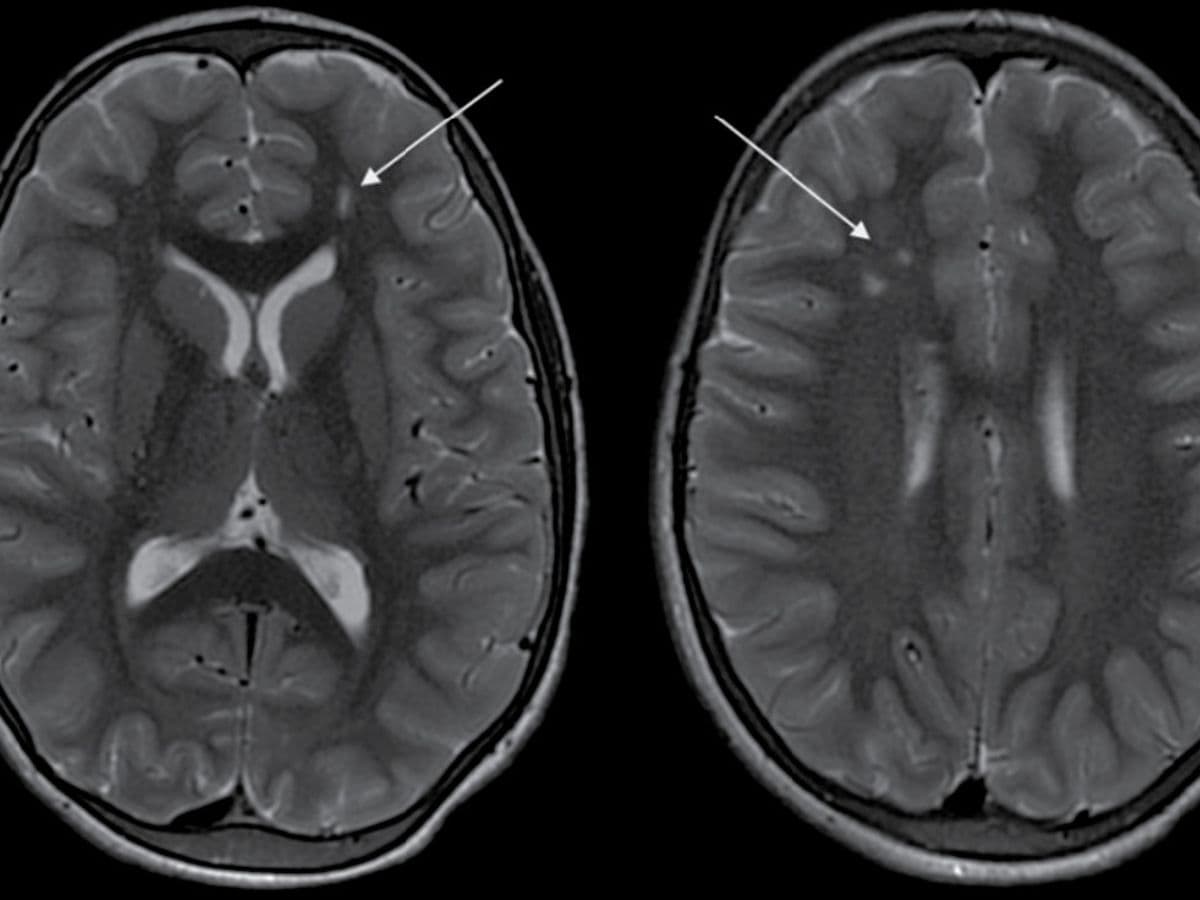

Bangalore, 22nd January, 2025: In a compelling case that underscores the importance of early diagnosis and expert intervention, an 11-year-old boy from Devanahalli Taluk, overcame the challenges posed by Moyamoya disease—a rare cerebrovascular disorder often leading to continuous strokes. Known to have a prevalence rate of 0.35 to 0.94 per 100,000 people, mainly in the areas of Japan and Korea, Moyamoya disease manifests itself via gradual narrowing of arteries supplying blood to the brain. Arjun (name changed) experienced an episode of seizure a year back which was progressively followed by a decline in his ability to see and weakness on the left side of his body over the course of the year. A CT Angiogram at Aster Whitefield Hospital showed a “puff of smoke” appearance - a hallmark sign of Moyamoya disease, hence confirming the diagnosis.

This rare and unique disease mostly affects children around the age of 10 years and adults around the age of 40 years while progressing without warning, necessitating prompt and precise medical intervention. Moyamoya disease causes narrowing of key brain arteries, prompting the brain to form smaller compensatory blood vessels to meet its oxygen needs. These new vessels, however, are often insufficient, appearing as a “puff of smoke” in imaging scans. When the brain’s demand for blood outpaces the supply, patients experience strokes or other neurological events, as in Arjun’s case. Left untreated, Moyamoya can lead to recurring strokes, disability, and even death, making early diagnosis critical to altering the disease's course.